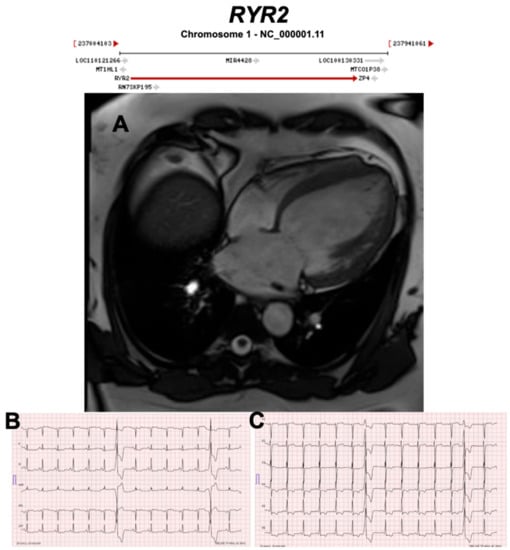

3.2.10. Ryanodine Receptor 2 (RYR2) (Encoded by RYR2)

- Bhuiyan, Z.A.; van den Berg, M.P.; van Tintelen, J.P.; Bink-Boelkens, M.T.; Wiesfeld, A.C.; Alders, M.; Postma, A.V.; van Langen, I.; Mannens, M.M.; Wilde, A.A. Expanding spectrum of human RYR2-related disease: New electrocardiographic, structural, and genetic features. Circulation 2007, 116, 1569–1576. [Google Scholar] [CrossRef] [PubMed]

| RYR2 | Calcium Regulation | 9% | AD | Exon 3 deletion DCM | ARVC2 | 1q43; 107 | CPVT | Refuted for ARVC, Definitive for CPVT |

| Conflicting evidence of misdiagnosis CPVT as ARVC with the exception of exon 3 deletions associated with structural abnormalities. | ||||||||